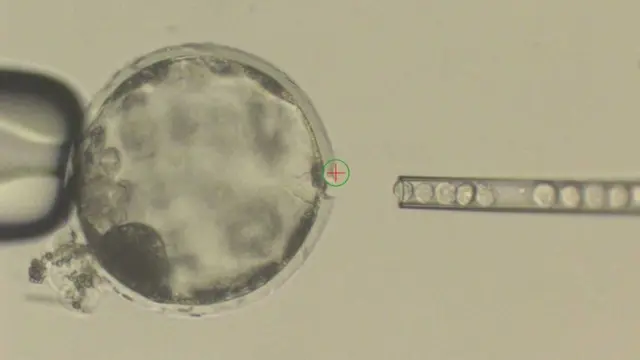

Ученые вырастили первые в мире эмбрионы-химеры, состоящие из клеток человека и свиньи, говорится в исследовании, опубликованном в журнале the Cell.

Ученые вживляли человеческие стволовые клетки в эмбрионы свиньи. В результате получалась смесь из человеческих и свиных клеток, которую на месяц подсаживали самке свиньи.

Этот процесс оказался очень неэффективным: из 2 075 подсаженных эмбрионов в течение 28 дней развивались лишь 186 штук.